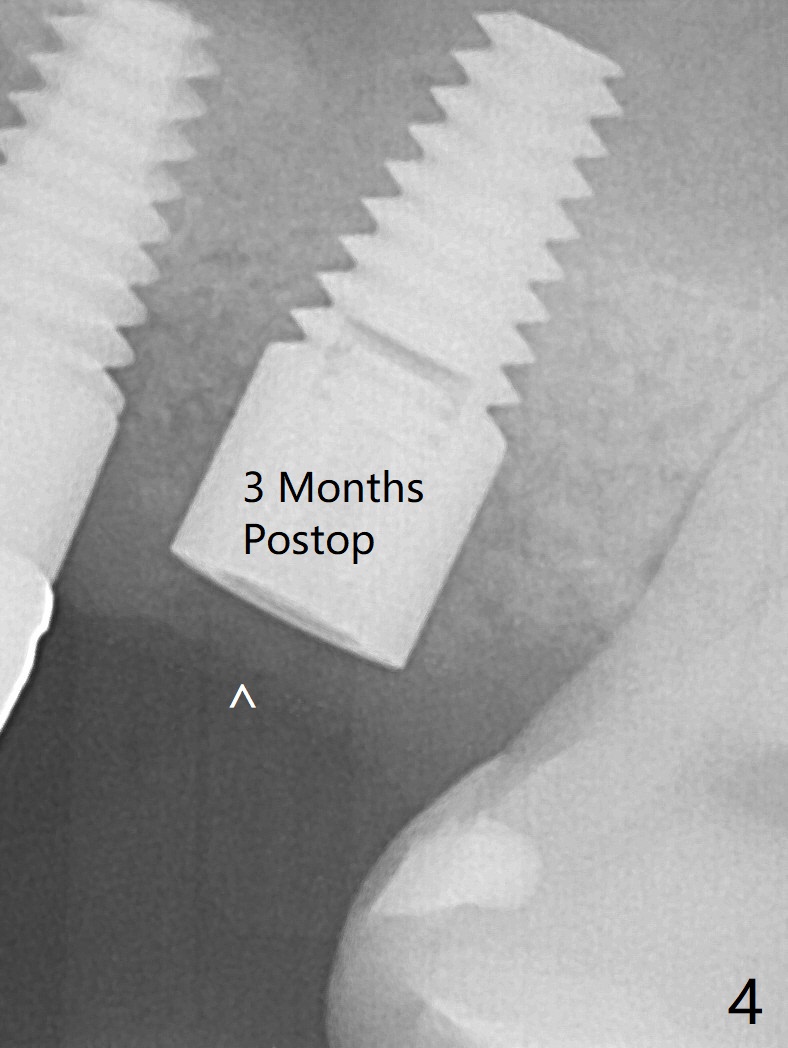

The ridge at #14 seems wide 6 months post implant removal and bone graft (before and after incision). In fact the palatal bone is low, which was the basis for periimplantitis. The new osteotomy is not initiated buccal enough. Immediate redo or guided surgery can avoid this complication. When a 4.5x14 mm tap is placed (Fig.1), the palatal threads are exposed. The buccal bone of the osteotomy has to be removed before placement of a 4.5x11 mm with 1 thread exposure palatal (Fig.2). Periimplantitis at #13 is found intraop (Fig.1 *). After removal of granulation tissue and use of Titanium brush, allograft is placed at #13 and 14 (Fig.2 ^) and is covered by PRF. Bone expansion is not conducted because of high bone density. If there is difficulty in restoration due to deep implant placement, it has to be backed up using torque wrench. The wound appears to heal by secondary intention 20 days postop (Fig.3). The implant is subgingival nearly 3 months postop (Fig.4 ^: gingival margin). It appears that the implant could be backed up (Fig.5,6). A 5 mm healing cuff is placed with Cetacaine and antibiotic ointment. The implant remains subgingival with the healing abutment 4 months postop. With Cetacaine and 2 gingival retraction cords, the implant margin is barely exposed. Large and deep gingivectomy is performed with Waterlase without too much pain. The gingival cuff is slightly erythematous and hemorrhagic on cementation (partially due to suboptimal oral hygiene, Fig.7). The margin is deep. Tatum implants are contraindicated when the gingiva is thick (Fig.8).